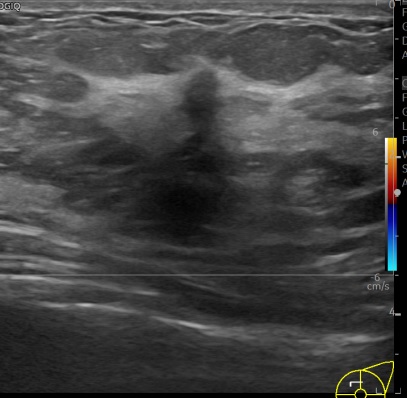

상기환자는 외부건진이상 조직검사 권유받아 내원하신 40대중반

여성분으로 의심스러운 좌측혹 조직검사 시행해  유방암 진단되었습니다